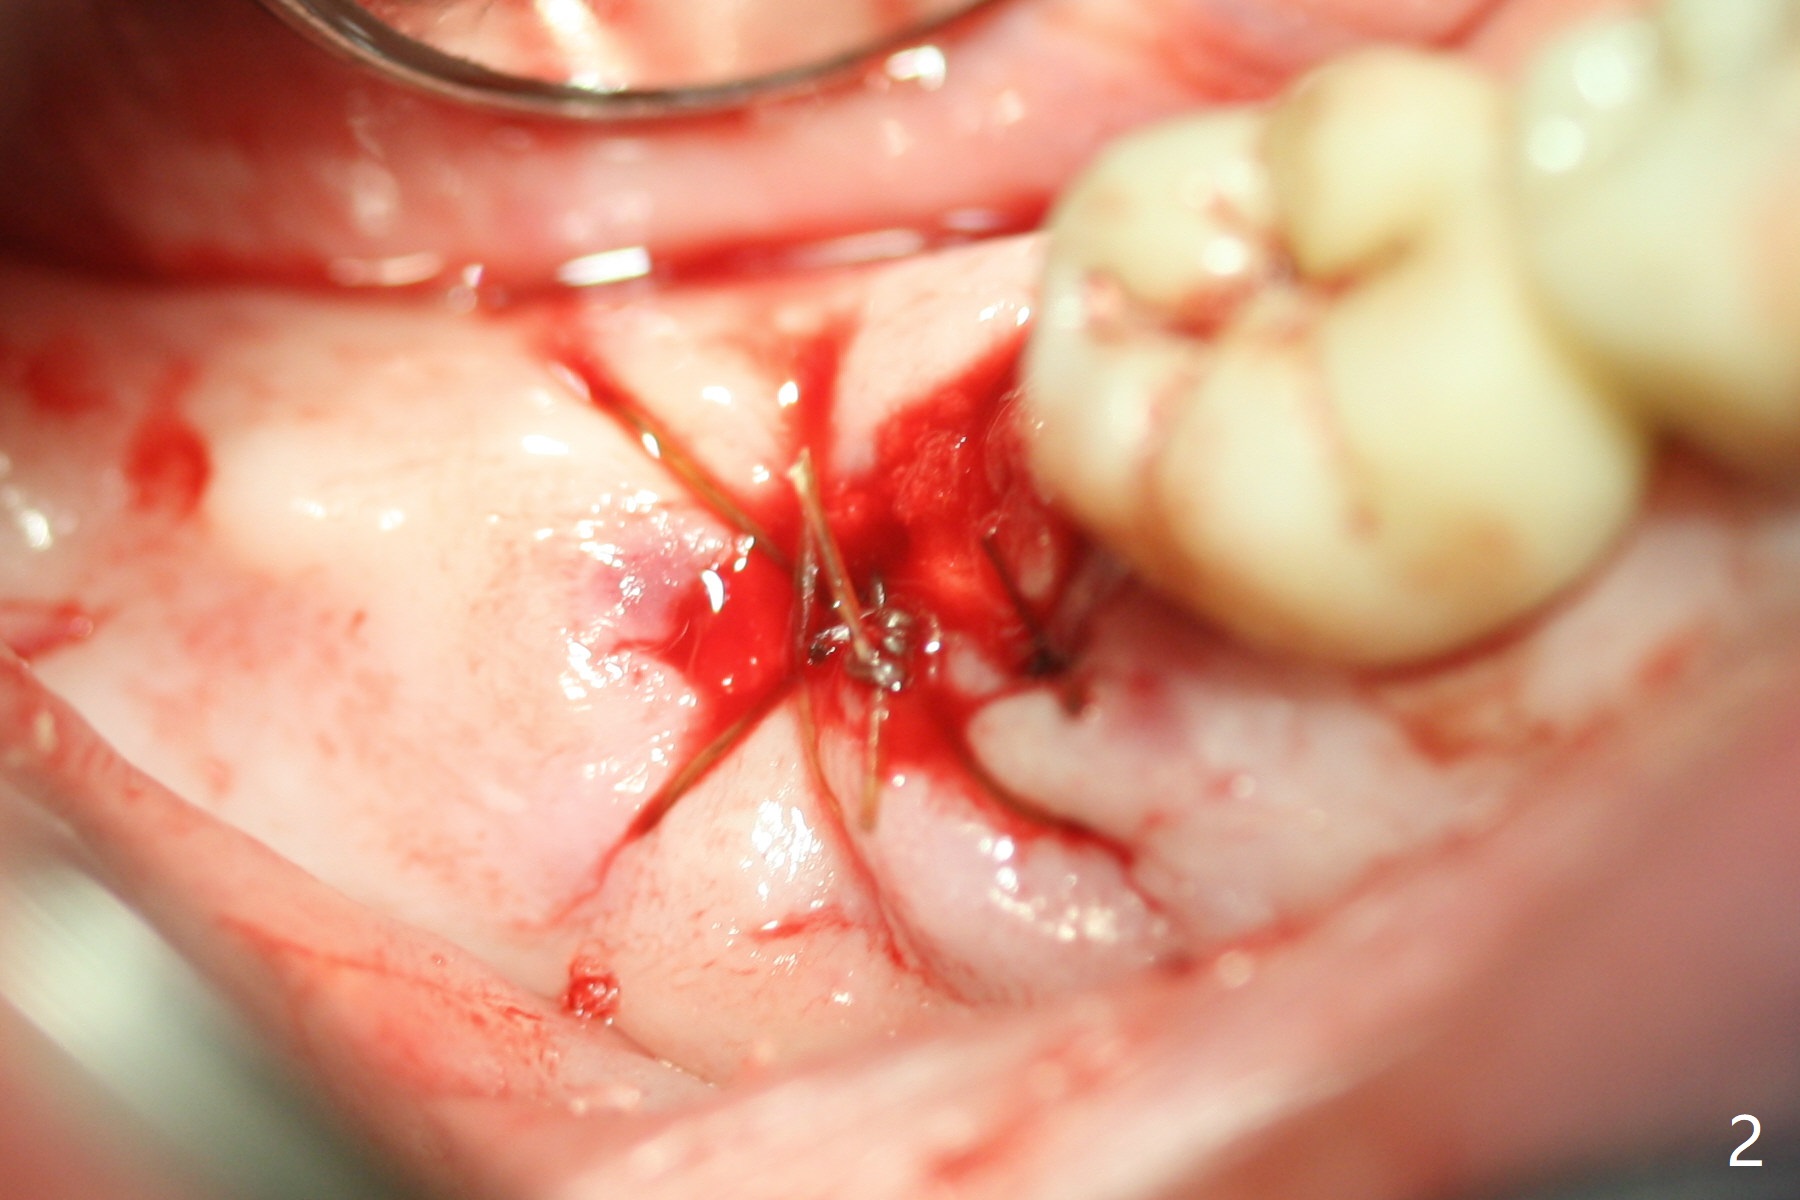

A 88-year-old man returns with pain and swelling (Fig.1), one year after diagnosis of #31 mesial root fracture. After discussion, the tooth is extracted with socket preservation (Vanilla graft mixed with Osteogen, covered with Osteogen plug and Collagen plug, Fig.2,3). The buccal crest is much lower than the lingual one. The socket opening reduces with resolution of 4-0 Chromic gut suture 1 week postop (Fig.4). The wound is wider with foul odor 2 weeks postop (data not shown). The socket and ridge shrink with loss of the bone graft 3 weeks postop (Fig.5). The bone volume reduces with buccal plate collapse 3 months postop (Fig.6,7). Immediate implant and provisional should be able to help restore the lost buccal plate. The buccal plate remains concave 5 months postop (Fig.8,9). The coronal section shows that there is space (Fig.10 *) buccal to the graft (G). A 2.0 mm pilot drill is used to create an initial osteotomy through the graft zone and in the beginning of the native bone (Fig.11,12). Use bone expanders (Fig.13 E) to push (arrowheads) and condense the graft bone and close the buccal gap. The apical portion of the osteotomy requires regular drills (Fig.14 D).